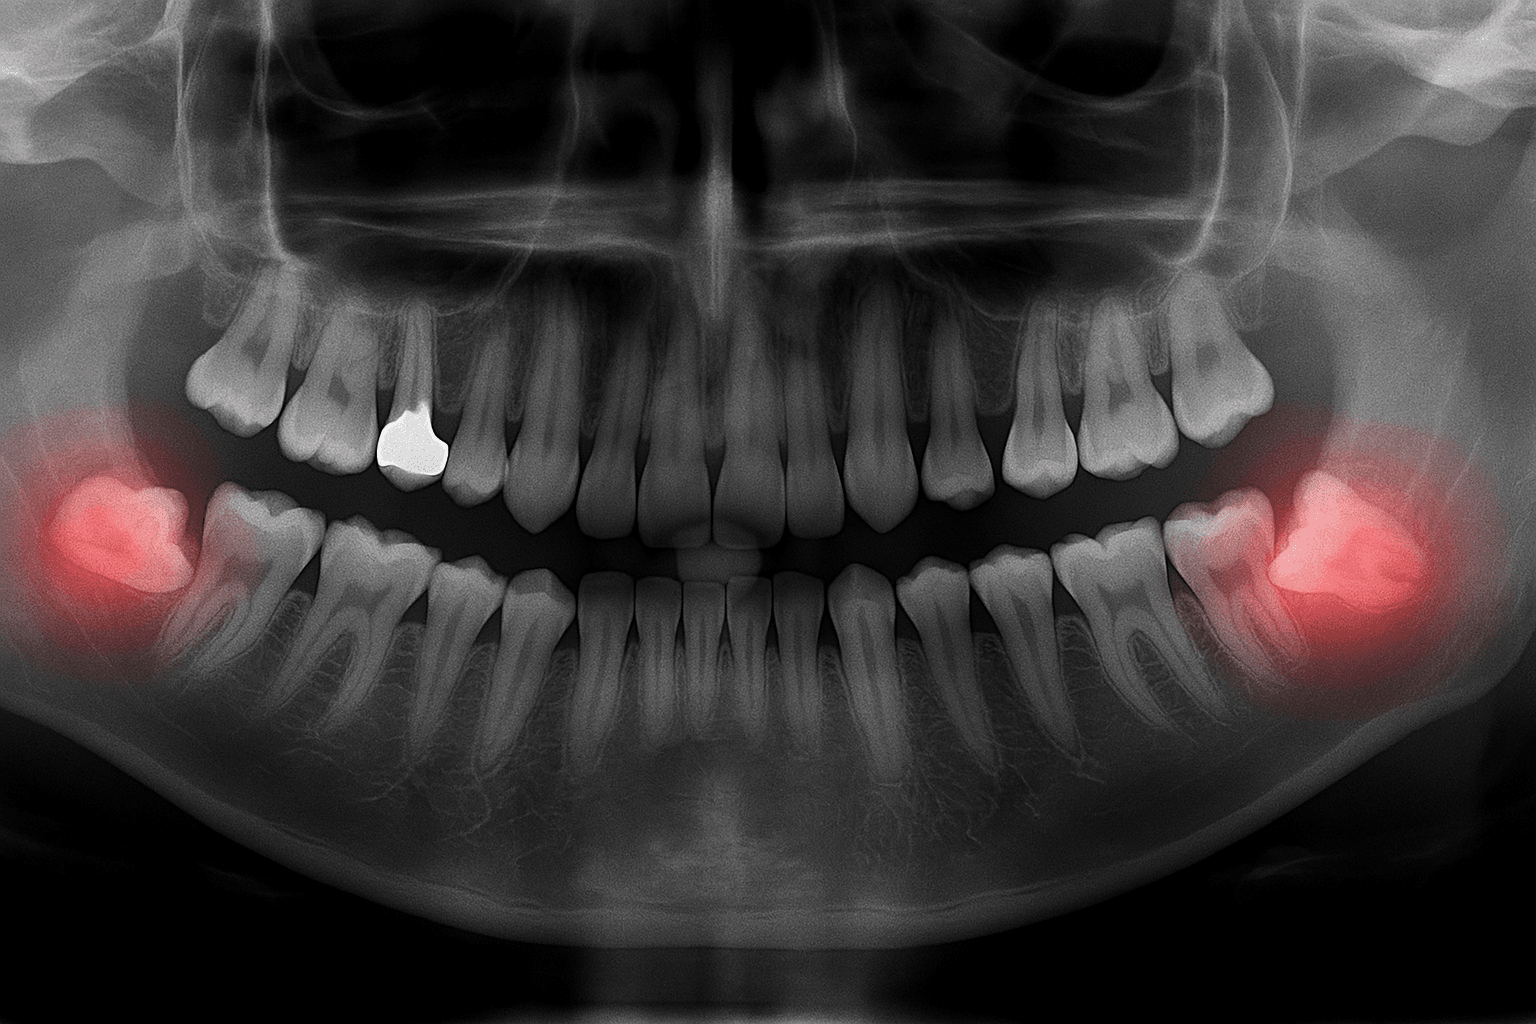

- • Dzięki tomografii CBCT możliwe jest uzyskanie szczegółowego obrazu struktur anatomicznych, co pozwala na precyzyjne zaplanowanie położenia implantu i bezpieczne przeprowadzenie zabiegu.